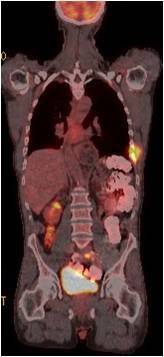

OEM-software supplier ContextVision, its sister provider of end user products SharpView, and the Massachusetts General Hospital are investigating advanced 3D image filtering as a means to boost productivity and improve image quality for MRI, as well as cut dose in CT.